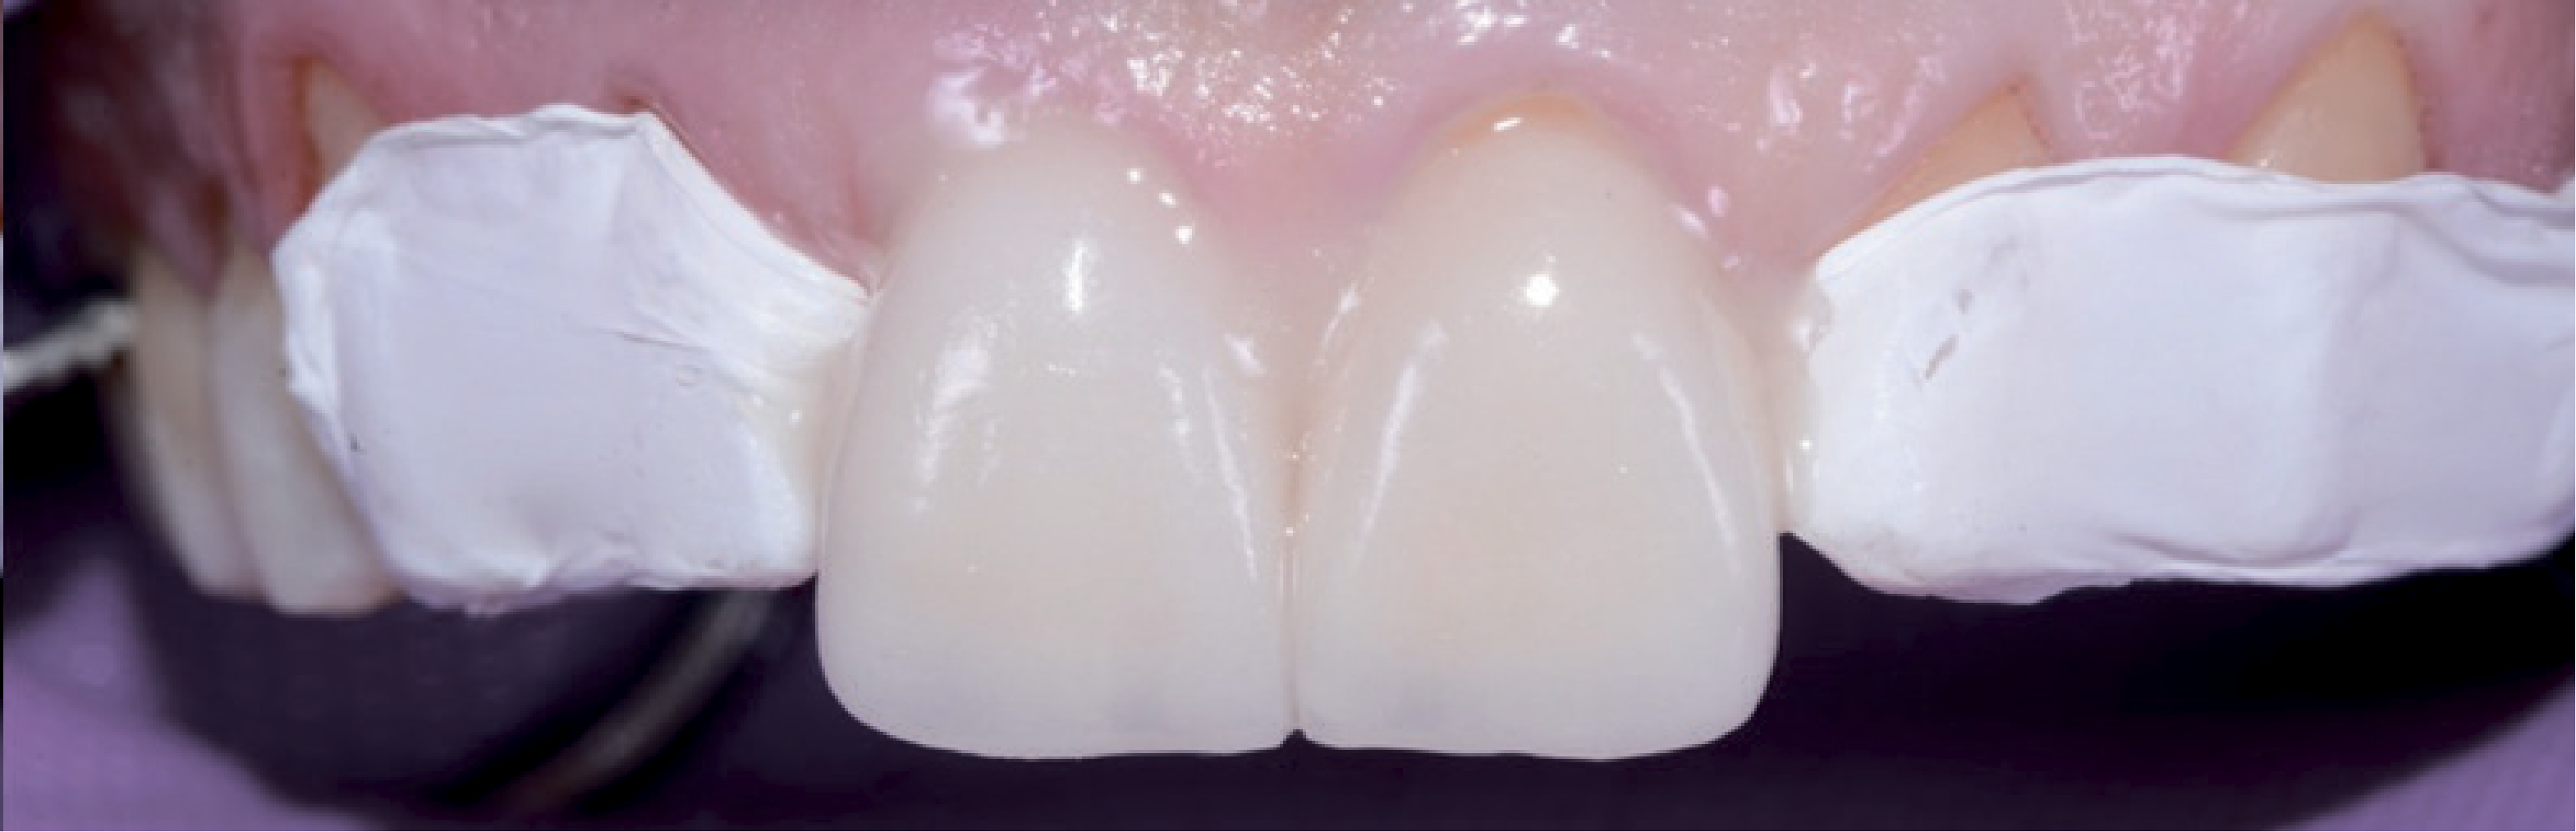

У стоматологічній лабораторії для зубів 15-25 були виготовлені пресовані вініри e-max, покриті полевошпатною порцеляною. Завдяки використанню техніки «spot etch» тимчасові реставрації вдалося легко видалити скалером. Відпрепаровану поверхню очистили матеріалом ConsepsisScrub (Ultradent). Для остаточного встановлення реставраційних конструкцій скористалися VitiqueCementationSystem (DMG). За допомогою пробних паст різних відтінків, аналогічних адгезивним цементам, за допомогою системи Vitique можна у всіх подробицях змоделювати остаточний результат. Оскільки порцелянові вініри тонкі та прозорі, цьому етапу приділили максимум уваги. Щоб приміряти реставраційні конструкції, використовували примірочні пасти, які містять гліцерин і є у комплекті VitiqueCementationKit (DMG). Вони дозволяють ідеально змоделювати остаточний результат (мал. 17).

Коли посадка й колір вінірів були задовільними для пацієнта та лікаря, адгезивну фіксацію можна було виконати та отримати прогнозований результат. Кукси знову очистили струменем води, після чого зафіксували вініри. Вініри протравили 5% розчином фтористоводневої кислоти та силанізували системою з двох флаконів VitiqueSilane (DMG) для посилення міцності з'єднання. Протягом 20 секунд відпрепаровані ділянки перебували під впливом 37% фосфорної кислоти, щоб забезпечити адгезивне з'єднання з ТЕСО (DMG). Адгезивний засіб з одного флакона нанесли тонким шаром на 5 секунд. Перш за все, верхні центральні різці обробили одночасно, щоб гарантувати симетрію. Сусідні зуби закрили тефлоновою стрічкою (мал. 18).